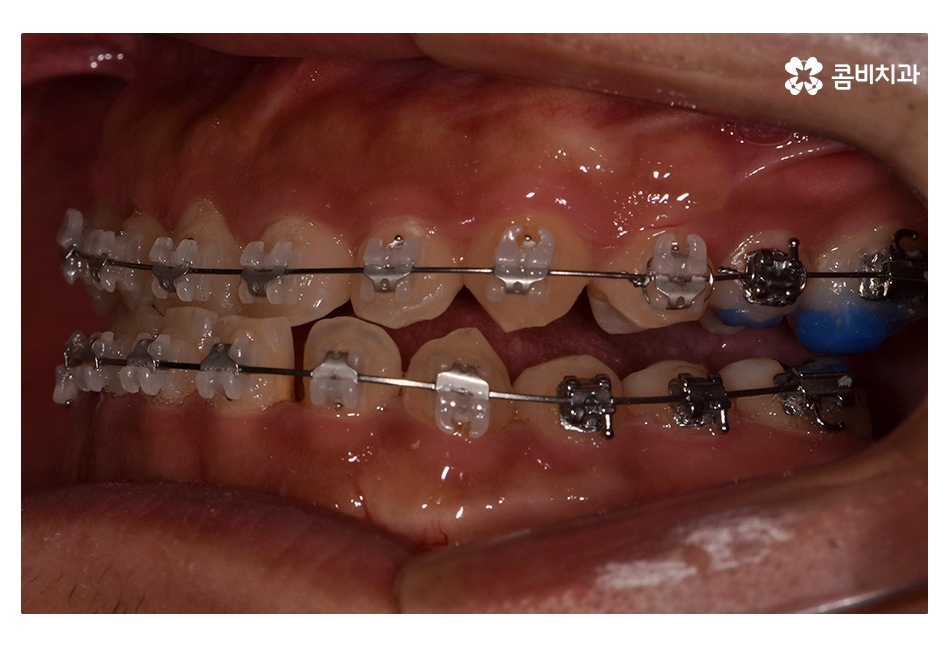

클리피씨교정이 진행되고 시간이 지날수록 아랫니가

점점 윗니에 덮이는 정상 교합의 상태로 개선되는 것을 볼 수 있는데요.

치아교정은 개인에 따라서 치료 기간이 달라지겠지만

위 환자분의 경우 수술과 병행되어 비발치 교정으로 진행되었기 때문에

약 1년 6개월 정도의 기간이 소요되었으며

교정 후 교합이 정상적으로 맞물리는 것을 확인할 수 있어요.

클리피씨교정은 와이어 교체가 간편하며 치아 색과

유사한 세라믹 재질을 사용하기 때문에 심미적으로도 우수한 편이며